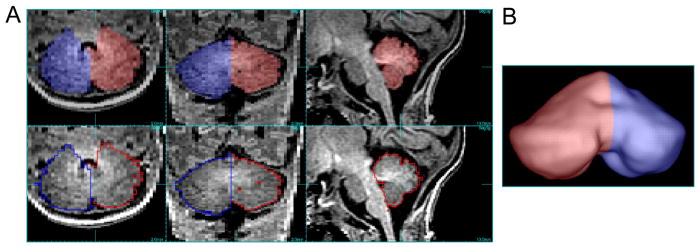

High-resolution T1-weighted SPGR sequences were used to perform 3D tracings of the cerebellar hemispheres using interactive semi-automated tools developed at UCSF (http://rview.colin-studholme.net). Tracings were performed by a single pediatric neurologist blinded to patient history (EWYT). Volumes were obtained by manual delineation of the cerebellum at each level using landmarks visualized in 3-dimensions (Figure 1). Cerebral spinal fluid spaces allowed delineation of the cerebellum from the surrounding structures. Each hemisphere was traced separately, divided midline at the vermis. This technique had excellent reproducibility when tested by performing 10 tracings in a blinded manner from five different scans, with an intraclass correlation coefficient of 0.99.

Figure 1.

Volumetric tracings of left and right cerebellar hemispheres superimposed on 3D T1-weighted SPGR MR images. A. Left (red) and right (blue) cerebellar hemispheres are shown in axial, coronal, and mid-sagittal planes on this MRI scan performed at 38 weeks postmenstrual age. B. Resultant 3D rendered image.